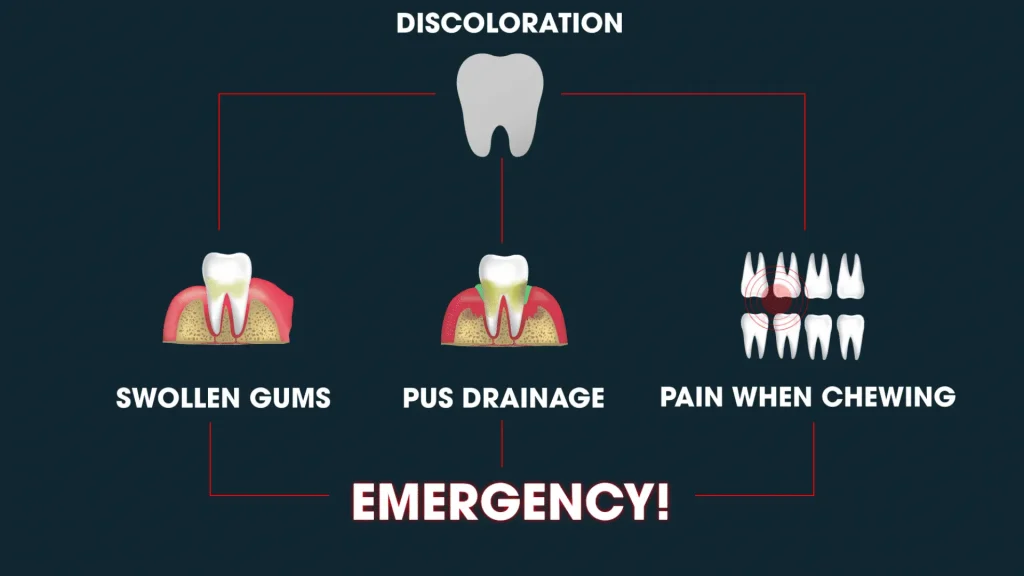

If discoloration is your only symptom, your grey tooth is likely not an emergency. However, if you have swelling in the gums around the grey tooth, pus drainage, or pain when you chew, you may have an urgent problem. Swelling indicates an active, spreading infection that has progressed past the internal spaces of the tooth and into the jawbone.